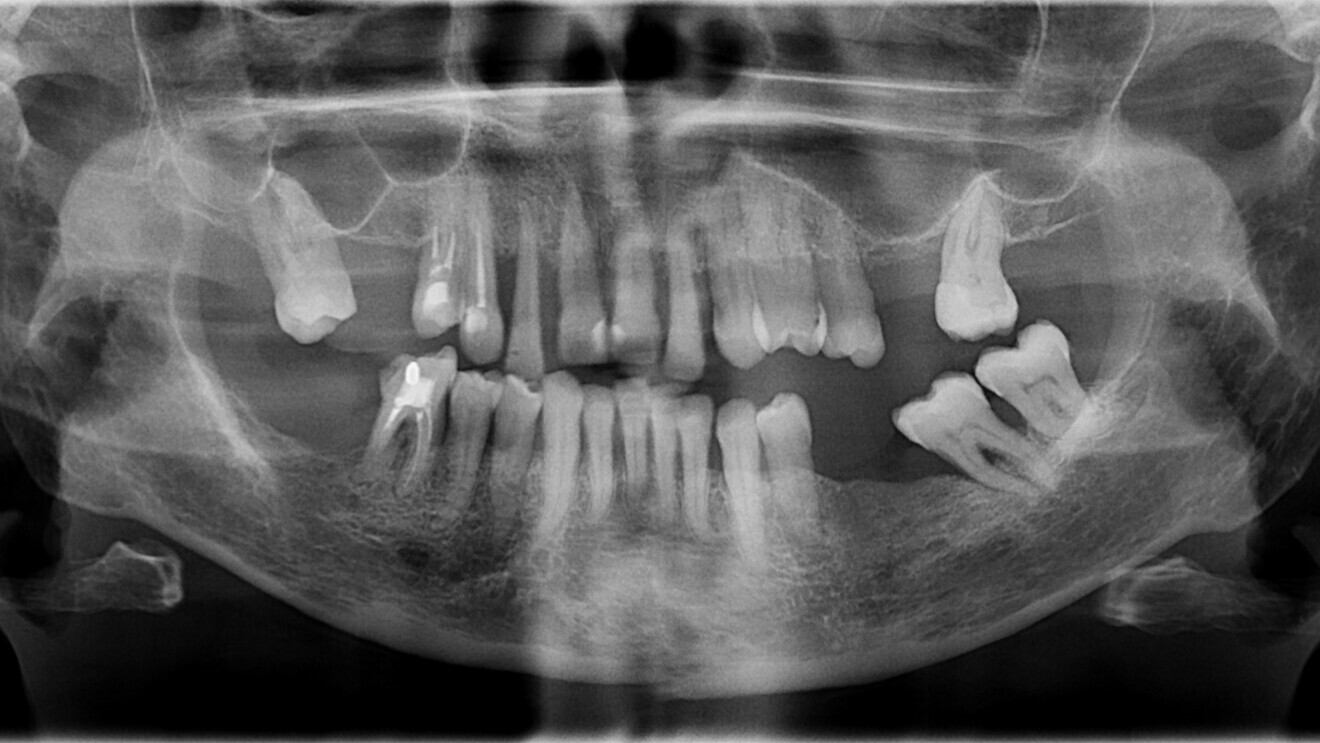

Fig. 2: Panoramic radiograph before treatment.

After a thorough anamnesis, clinical evaluation and radiographic examination (Fig. 2), the patient was diagnosed with Stage IV, Grade C periodontitis. After a complete periodontal cleaning and full-mouth disinfection, it became evident that none of the teeth in her upper jaw were salvageable.